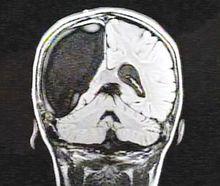

顯示右腦缺失的醫學掃描照片左右腦具有功能互補關係, 即使切除一側腦體也可以照常生活。

據報導,美國女孩卡梅倫·莫特切除了右腦依然照常生活。她患上拉斯穆森綜合徵,實施了大腦半球切除術。卡梅倫康復得相當順利,只留下輕微後遺症。

美國女孩傑西·霍爾由於罹患罕見的慢性局灶性腦炎,醫生冒險為她實施了大腦半球切除手術,徹底切除了其病變受損的右半腦。這個“半腦女孩”得以康復。據醫學專家分析,小傑西之所以得以康復,是因為她的左腦在術後“ 接管”了通常由右腦控制的工作,並正常發揮其功能。